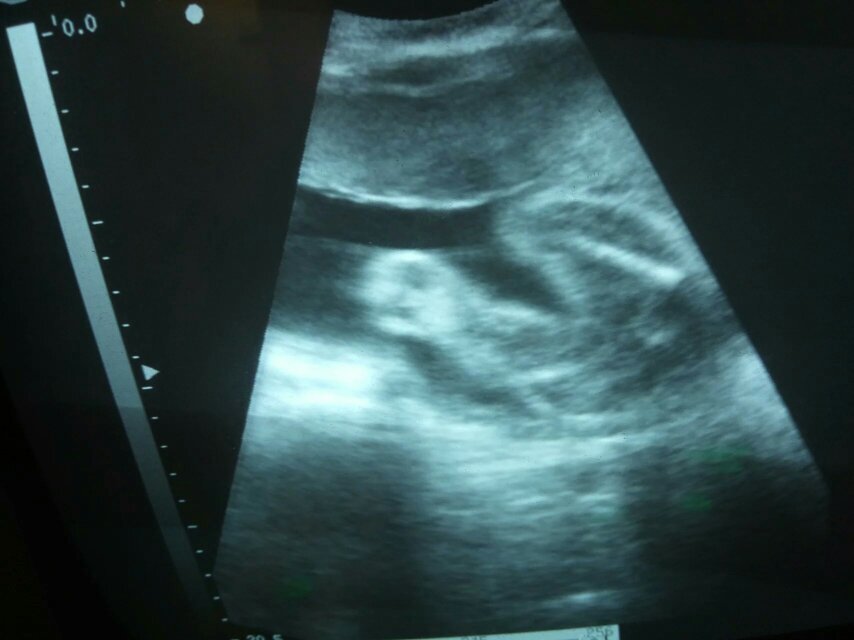

孕六个月黑白b超两次,她说十分清楚,就是女孩,有图,有懂得帮我看看,真的是女孩吗? 点击展开 匿名用户 2016-04-16 21:15 满意回答 亲相信科学吧,是男孩的话不到三个月就可以看出来 131*****262_t2Ki 2016-04-16 21:17 宝宝知道提示您:回答为网友贡献,仅供参考。 为您推荐: 其他回答 不懂,女孩子挺好的,现在女孩最吃香 称慧心_Y1Oo 2016-04-16 21:16 健康就好 匿名用户 2016-04-16 21:15 是女孩 匿名用户 2016-04-16 21:15 男女都一样 匿名用户 2016-04-16 21:15 相关问题 请问我怀孕六个月时去照黑白B超,医生说是女孩,但我的肚子很小又尖,朋友见到都说是男孩,究竟B超准不准 怀孕到现在长了16斤,孕30+3天,16周B超是女孩,自己希望是个男孩,保佑我生个男孩! 怀孕40天,B超孕囊大小1 2*0 7*1 0cm,是不是小了?能看出来是男孩还是女孩吗?